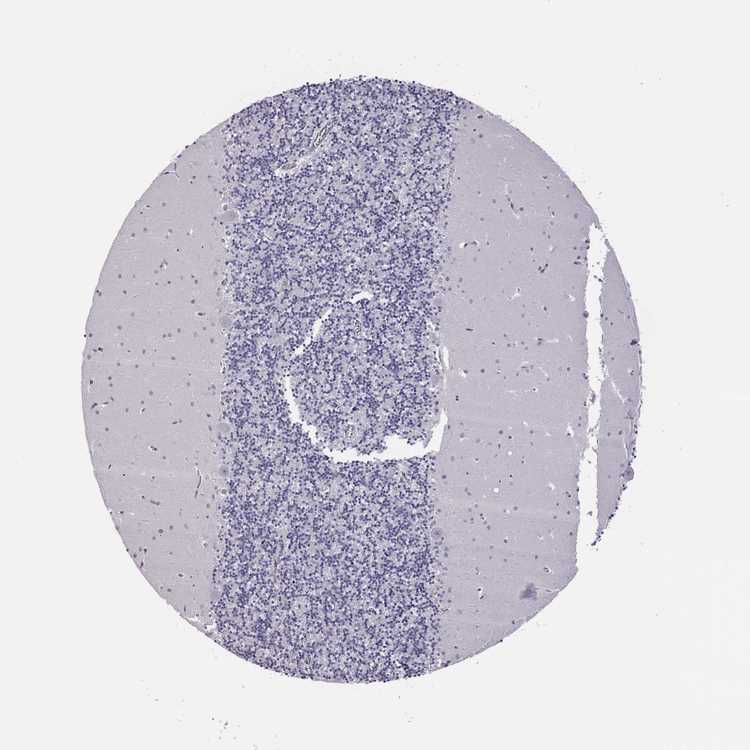

CEREBELLUM - Antibody stainingi

Antibody staining in the annotated cell types in the current human tissue is reported as not detected, low, medium, or high, based on conventional immunohistochemistry profiling in selected tissues. This score is based on the combination of the staining intensity and fraction of stained cells.

Each image is clickable and will lead to virtual microscopy that enables deeper exploration of all samples and also displays staining intensity scores, fraction scores and subcellular localization as well as patient and tissue information for each sample.

Antibody HPA008879

Purkinje cells Not detected

Cells in granular layer Not detected

Cells in molecular layer Not detected